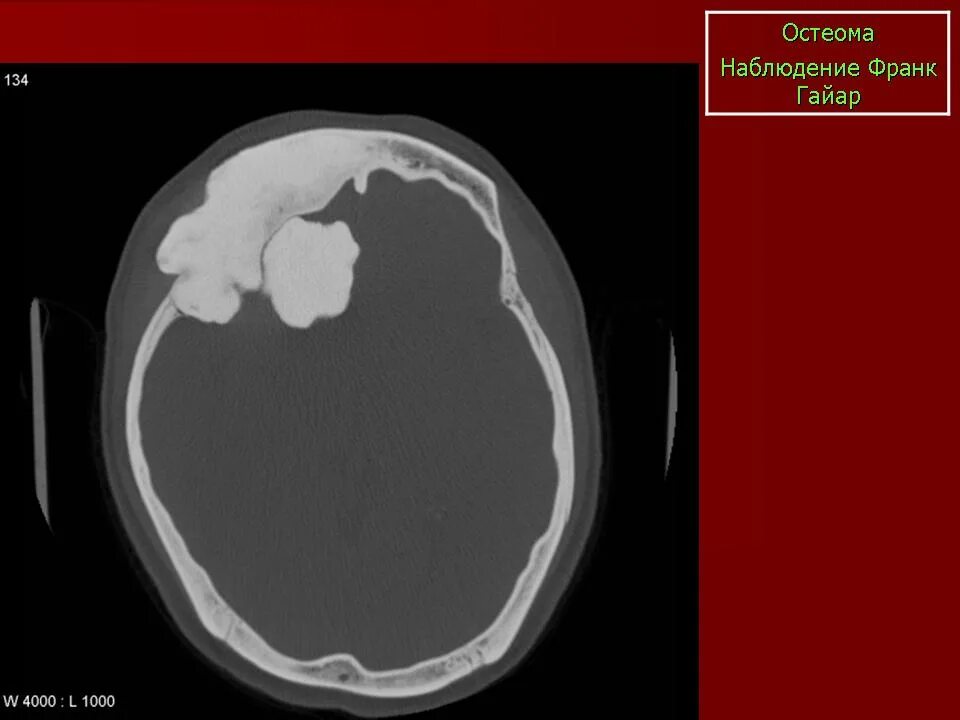

Остеома мрт